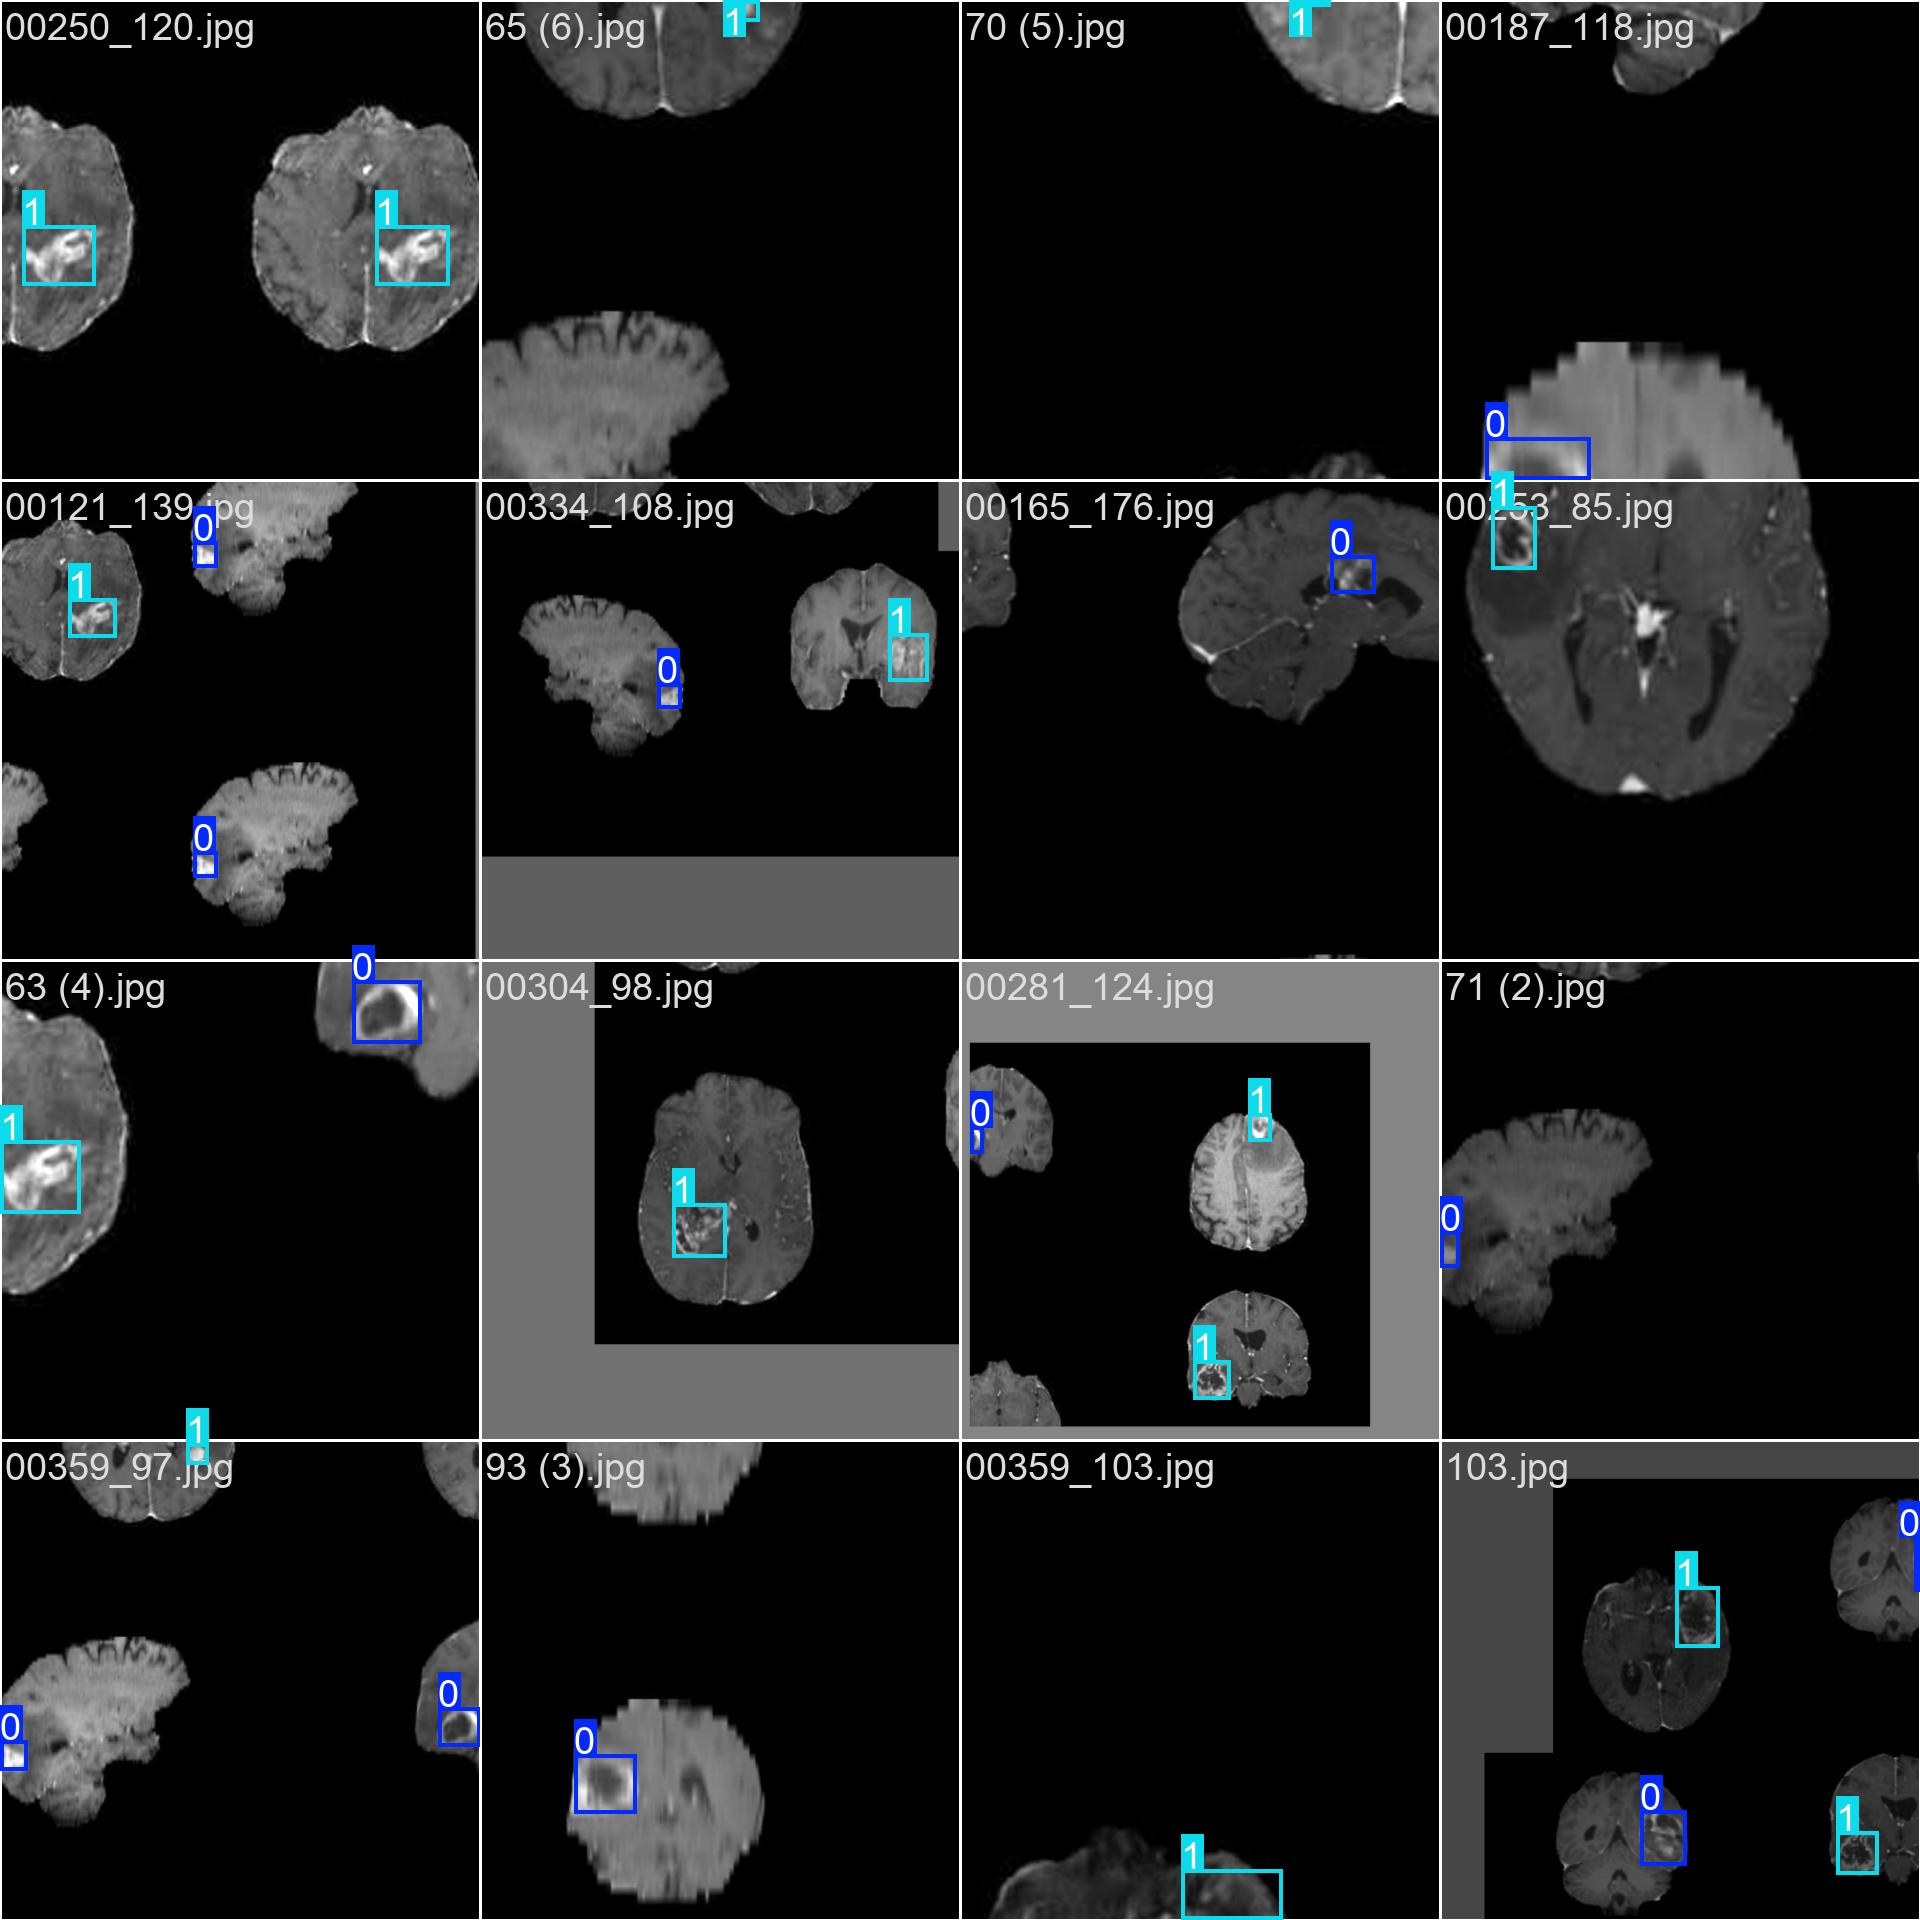

3.2 数据标注

使用标注工具(如 LabelImg, CVAT, Roboflow 等)对图像中的每一个肿瘤区域进行标注。

-

每个肿瘤需框出其边界(Bounding Box)

根据临床标准赋予类别标签:

negative或positive -

标注格式

:YOLO 使用

.txt文件存储标注信息,格式为:

txt<class_id> <x_center> <y_center> <width> <height>所有坐标值都是相对于图像宽高的归一化值(0-1)。

class_id = 0→negativeclass_id = 1→positive

3.3 数据集划分

将数据集划分为训练集(train)、验证集(val)和测试集(test),通常比例为 7:2:1 或 8:1:1。